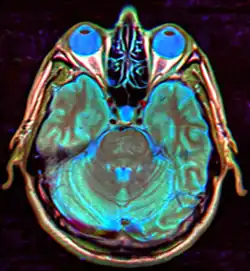

MRI of Empty Sella

Empty sella in MRI